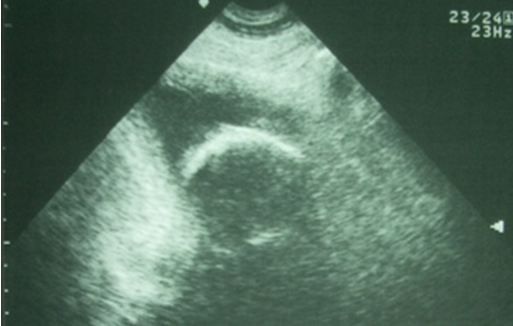

A 63-year-old man with hypospadias presents with ischuria x2 days but his bladder is barely enlarged. What do you see on the ultrasound?

He is in mild respiratory distress, but vital signs and pulse-ox are normal. He has both pulmonary rales and peripheral edema, but his heart sounds are normal. Despite his hypospadias, his bladder doesn’t feel enlarged.

You order a cath urinalysis, a chest film, and some blood work. The nurse is unable to pass a standard Foley or a coude (French for “elbow”) catheter, and asks if you could try the Foley and/or do a quick bedside ultrasound of his bladder. You pick option two and obtain the following sonographic image (Figure, above).

A. What does the ultrasound show?

B. What should be your next step or steps?